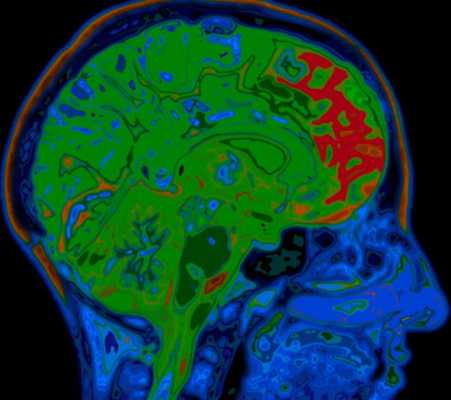

МРТ головного мозга. Т2-взвешенная сагиттальная МРТ. Болезнь Пика. Цветовая обработка изображения.

Прогрессирующий надъядерный паралич проявляется в виде нарушения взора вверх, экстрапирамидной симптоматики и умственных нарушениях. Заболевание развивается у лиц около 60 лет. Этиология неизвестна, почти все случаи спорадические. Частота 1-1,5 случаев на 100 тыс. населения. Заболевание характеризуется патологическим скопление в головном мозге тау-протеина. При МРТ головного мозга наблюдается диффузная атрофия, причем на сагиттальных Т1-взвешенных МРТ отмечается характерный симптом “пингвина”. Атрофические изменения моста и среднего мозга приводят к расширению водопровода и III желудочка, контур которых напоминает очертания пингвина.

МРТ головного мозга. Т12-взвешенная сагиттальная МРТ. Прогрессирующий надъядерный паралич. Симптом “пингвина”.